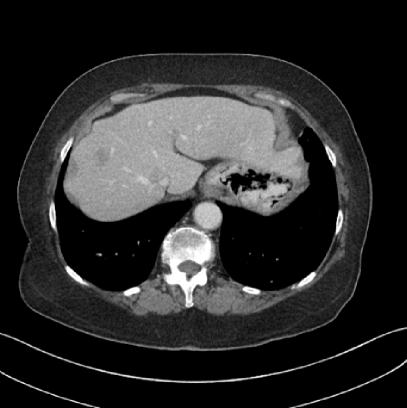

Figure 14: Qualitative clinical results from a thoracic CT staging dataset for a 12-year-old with osteosarcoma with pulmonary metastases. The clinical standard hybrid IR is shown on the left and JENG is on the right. (a) The clinical standard hybrid IR in lung window with a window center of -600 HU and a window width of 1500 HU. (b) JENG at a resolution comparable to the clinical standard, but with less noise and fewer artifacts. (c) The clinical standard hybrid IR in soft tissue window with a window center of 55 HU and a window width of 440 HU. A metastatic lung cancer nodule can be found in the left upper lobe. (d) JENG in soft tissue window at a comparable resolution, but with less noise and fewer artifacts. Note that JENG is not fully corrected for beam hardening artifacts.

V.B. Clinical Cases

None of the spatial resolution and artifact reduction advantages would hold unless JENG shows image quality improvement over the clinical standard method on patient datasets. To do so, we evaluated JENG on 5 thoracic and 3 abdominal CT scans and all scans used the same parameter settings as those for the ACR phantom scan, except that the tube current and the pitch is modulated individually for each patient. The exact experiment setup was discussed in Sec. IV.. For a fair image quality comparison, we matched the resolution of JENG and the clinical standard hybrid IR and studied their image noise and artifacts.